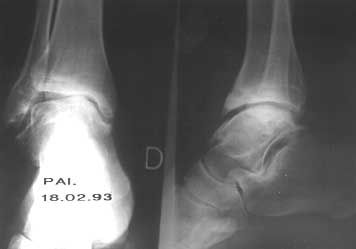

Manifestations ostéo-articulaires de la drépanocytose